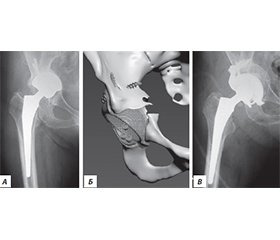

Актуальність. Ендопротезування кульшового суглоба сьогодні є одним із найбільш поширених і водночас ефективних методів лікування. Проте у віддалені терміни після операції виникає проблема розвитку нестабільності елементів протеза, що потребує повторних оперативних втручань, які належать до категорії складних і технічно трудомістких. Мета дослідження: на основі власного досвіду ревізійного ендопротезування кульшового суглоба та даних літератури обговорити питання планування і вибору тактики оперативного лікування для покращення результатів. Матеріали та методи. Було проаналізовано результати 146 ревізійних ендопротезувань кульшового суглоба у пацієнтів з асептичною нестабільністю елементів протеза за 11 років (2012–2022). Серед обстежених було 93 жінки та 53 чоловіки, вік пацієнтів коливався від 24 до 82 років (середній вік становив 64,5 року). Функціональне відновлення хворих оцінювали за шкалою Harris Hip Score. Результати. Нестабільність ацетабулярного компонента й ніжки протеза спостерігали у 34 пацієнтів, лише ацетабулярного компонента — у 48 осіб, лише ніжки — у 32 хворих, вивих протеза — у 9, стирання поліетиленового вкладиша — у 5, перелом керамічної головки — у 2, перелом ніжки протеза — в 1, перипротезні переломи — у 15 пацієнтів. Середній показник шкали Harris Hip Score становив 79,3 бала (95% довірчий інтервал: 73,9–84,7). Відмінні або добрі результати досягнуто у 52,8 % пацієнтів, задовільні — у 29,5 %, незадовільні — у 17,8 %. Загальна частота післяопераційних ускладнень становила 7,53 %. Висновки. У ревізійному ендопротезуванні доцільно віддавати перевагу безцементним системам фіксації з обов’язковим застосуванням кісткової пластики при дефіциті кісткової тканини. Найбільш ефективними виявилися ацетабулярні чашки з покриттям екструдованим титаном, а також ревізійні й індивідуально виготовлені конструкції. При ревізії стегнового компонента ніжка Wagner продемонструвала стабільні клінічні результати та надійність фіксації.

Background. Hip arthroplasty is one of the most common and effective surgical methods of treatment. However, over time, the problem of prosthetic component instability arises, requiring revision procedures. The aim was to analyze own experience of revision hip arthroplasty and literature data, with a focus on planning and surgical strategy to improve outcomes. Materials and methods. We analyzed the results of 146 revision hip arthroplasties performed in patients with aseptic prosthetic component instability in 2012–2022. The study cohort included 93 women and 53 men, aged 24–82 years (mean age 64.5). The functional recovery of patients was assessed using the Harris Hip Score scale. Results. Instability of both the acetabular component and femoral stem was observed in 34 patients; isolated acetabular component instability in 48; isolated femoral stem instability in 32; prosthetic dislocation in 9; polyethylene liner wear in 5; ceramic head fracture in 2; femoral stem fracture in 1; and periprosthetic fractures in 15 patients. The mean Harris Hip Score was 79.31 units (95% CI: 73.9–84.7). More than half of the patients (52.8 %) achieved excellent or good results, 29.5 % — satisfactory, and 17.8 % — unsatisfactory. The overall rate of postoperative complications was 7.53 %. Conclusion. In revision hip arthroplasty, preference should be given to cementless fixation systems with mandatory bone grafting in cases of bone deficiency. The most effective implants were acetabular cups with extruded titanium coating, as well as revision and custom-made components. In femoral component revisions, the Wagner stem demonstrated stable clinical outcomes and reliable fixation.